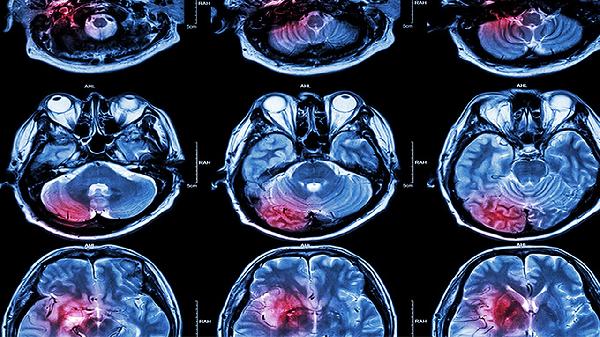

饮食宜选择高蛋白、高维生素食物如鱼肉蛋奶和深色蔬菜,避免酒精和咖啡因。康复期可进行太极拳、散步等低强度运动,从每日10分钟逐步增加至30分钟。保持规律作息,睡眠时垫高床头15-30度。定期复查头颅CT或MRI评估恢复情况,若出现持续呕吐、肢体无力等症状需立即就诊。